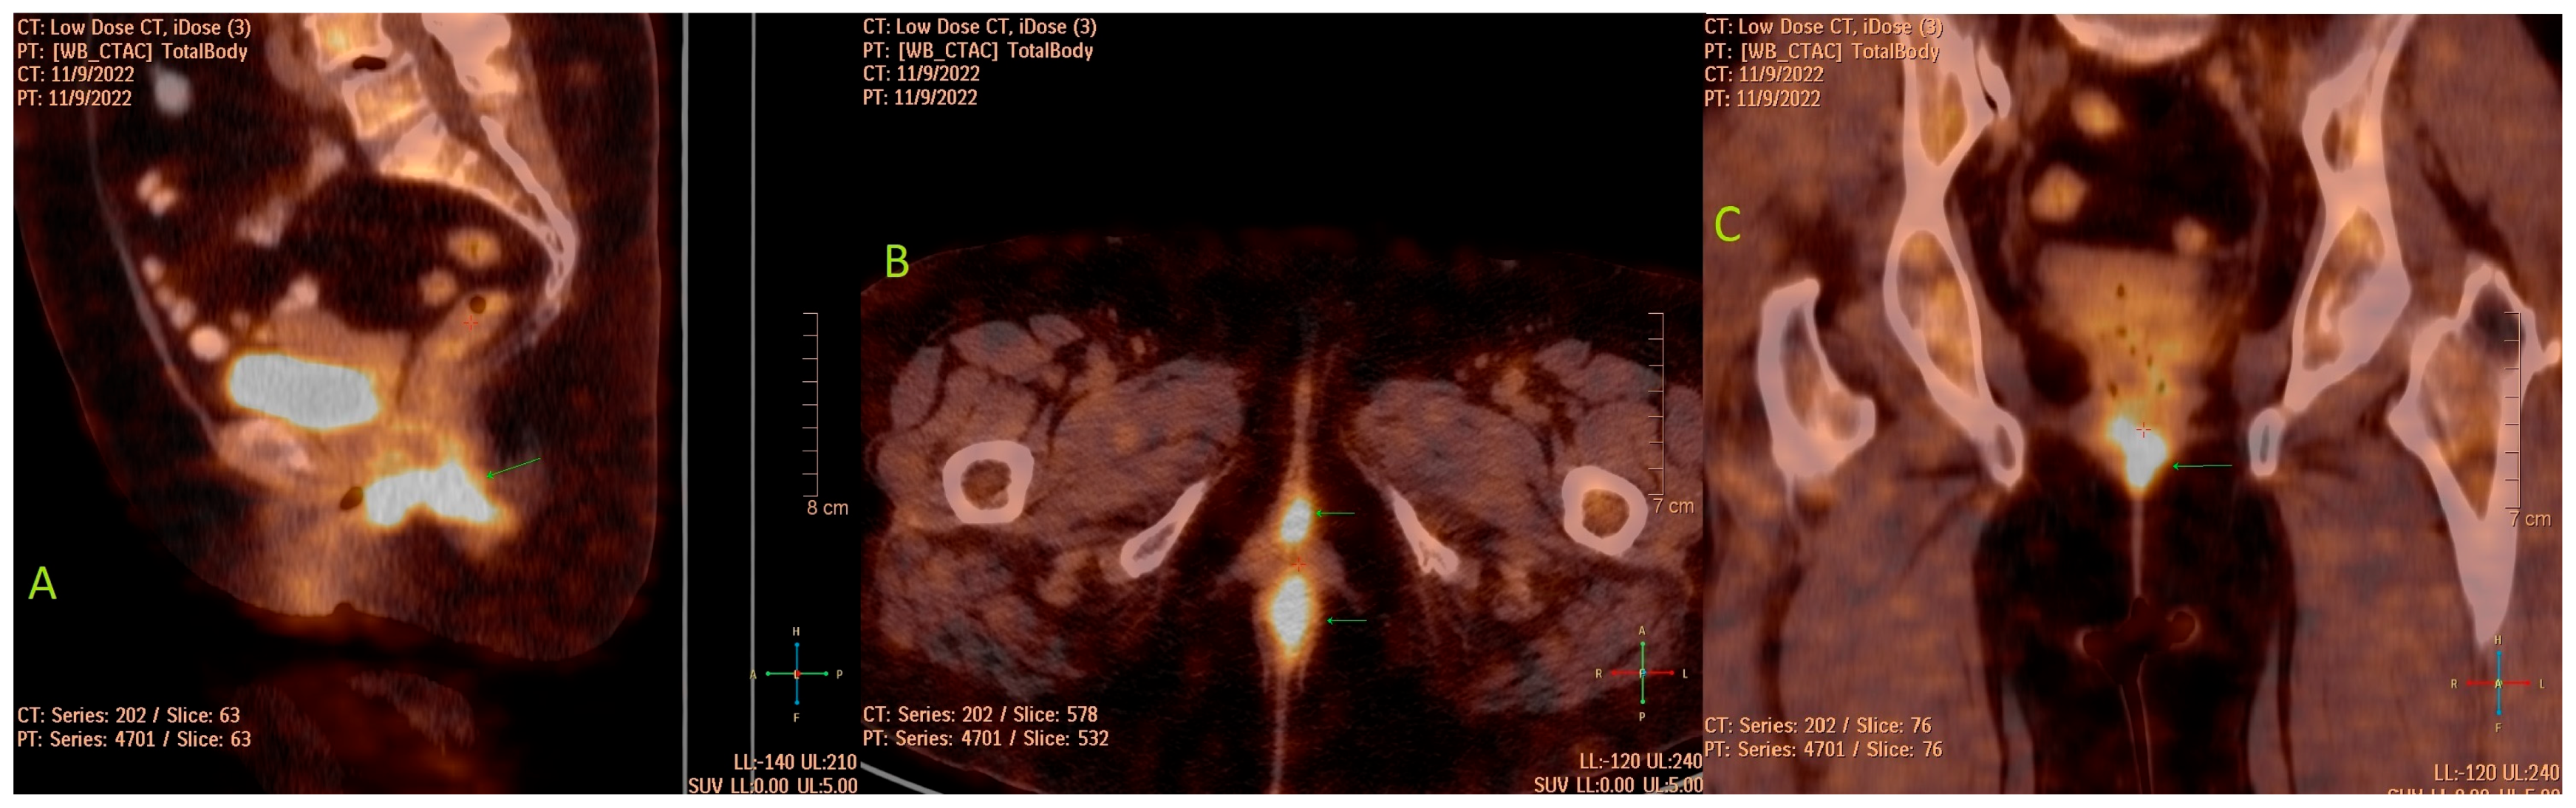

Primary Vaginal Mucinous Adenocarcinoma of Intestinal Type—Clinical, Radiological and Morphological Aspects

2. Case Presentation